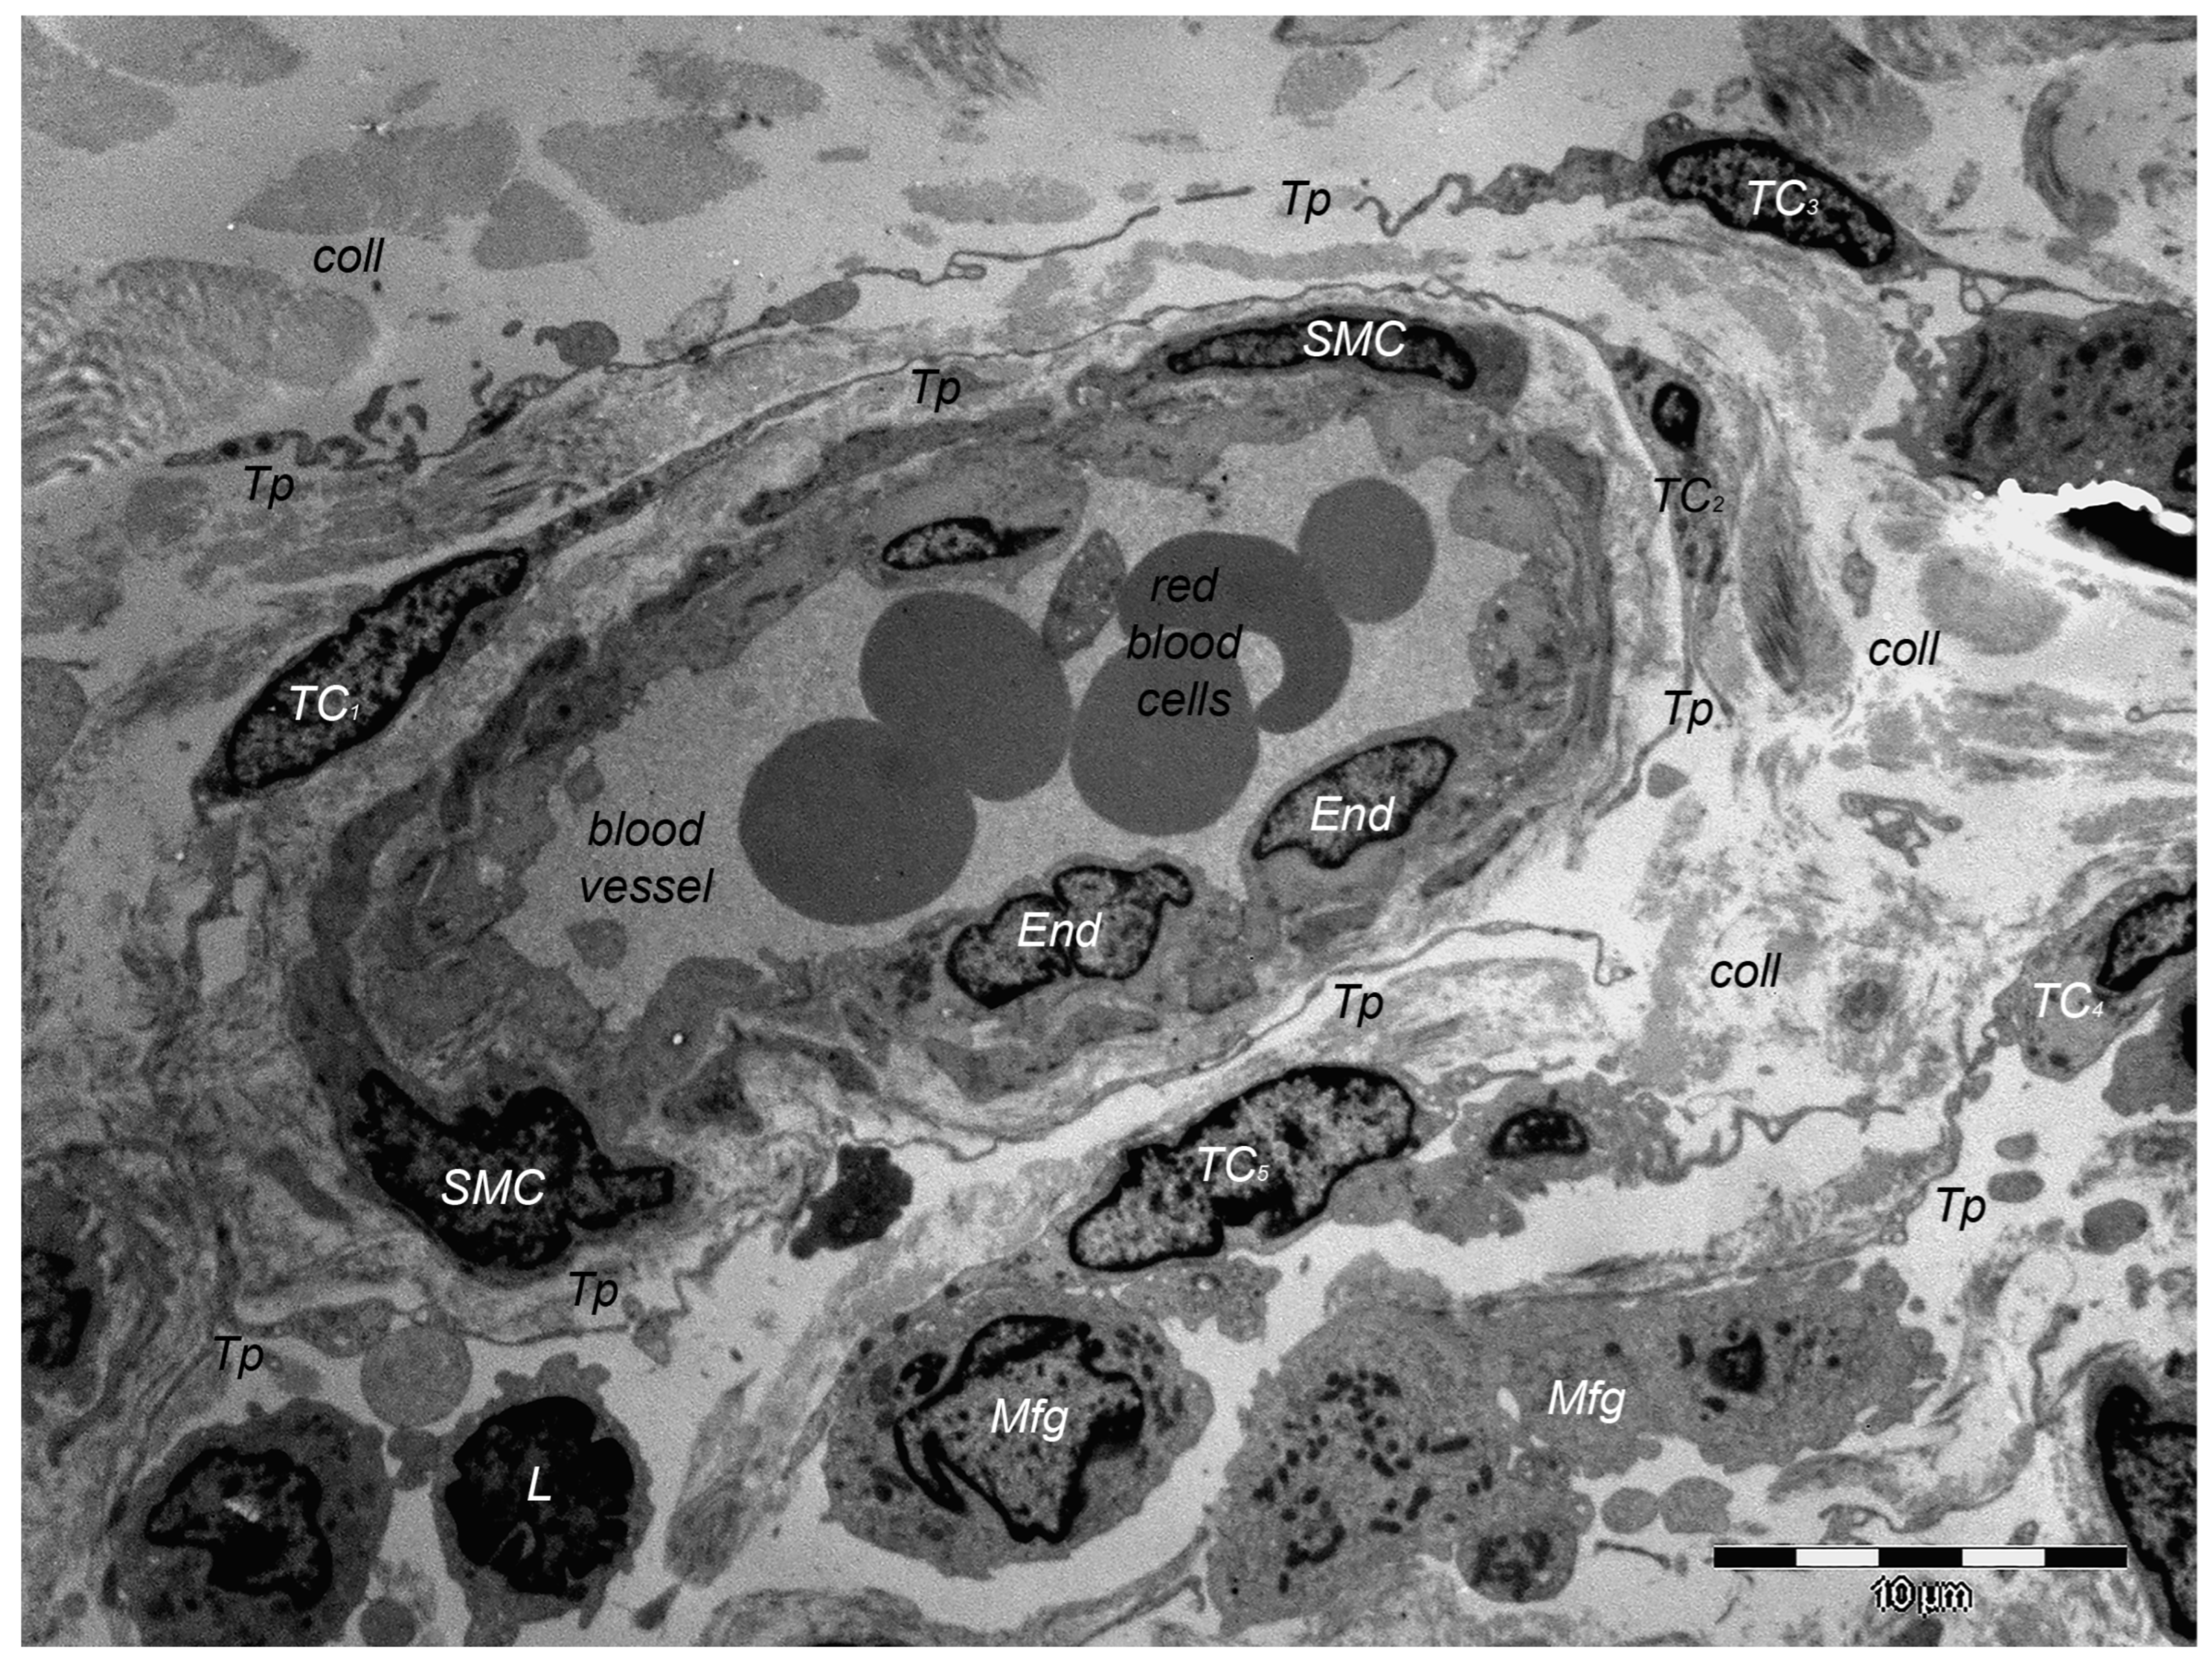

Over one decade ago, a distinct type of interstitial cell was initially documented in the stroma of few different peri-digestive organs [248] and were named telocytes (TCs) due to their morphology and location within tissues. Morphologically, their most prominent trait is the presence of very long cellular prolongations featured by a particular long-lump aspect—termed telopodes (Tps). From the peri-digestive compartment, their presence was afterwards documented in many different other organs from different species, including the (human) skin [249,250,251,252,253,254,255,256,257,258,259,260,261,262,263,264,265,266,267,268,269,270,271,272,273,274,275]. Interestingly, in all these locations, TCs display the same peculiar structural and ultrastructural features, as described in other organs, only with some minor variation in terms of their immunohistochemical phenotype [251,276,277,278,279,280]. Since their presence always features the stroma (connective tissue) of organs, it was understandable to find TCs within skin dermal layers [276,281]. In this location, TCs are grossly distributed in the deeper reticular dermis, in close vicinity to hair follicles strictly boarding the glassy membrane of the hair follicle (Figure 2), sweat glands (Figure 3), or sebaceous glands [282]. TCs are less dense in the superficial papillary dermis. Powerful and complex scanning electron microscopy techniques gave valuable conformational details about TCs and the spatial conformation of their Tps (as they are mostly veil-like structures rather than thread-like cellular prolongations [282]. Also, these techniques proved the complex three-dimensional disposal of dermal Tps (Figure 4), and their disposal in a network involving other TCs (by their Tps) and/or other types of interstitial cells, nerve cells, endothelial cells, or even immune cells [283,284].

Of course, corroborating structural data and immunohistochemical data many presumptive roles were suggested for dermal and non-dermal TCs, including intercellular signaling [285], interstitial homeostasis [11], vascular homeostasis [284], (neo)angiogenesis [12], wound healing [286]. Roles of nursing cells either in epithelial stem cells or implications in skin immune physiopathology (interactions with mast cells) are suggested, considering the cytokine/immune profile of TCs. Moreover, these hypotheses consider TC networking within normal tissue and, moreover, TC-specific localization within reticular dermis, in close vicinity to skin adnexa, blood vessels, and nerve endings (Figure 5). TCs’ paracrine secretion (shed vesicles) suggests roles for TCs in either controlling or modulating dermal Fbs’ activity or phenotype [276], or in organizing the dermal connective tissue environment [287]. Additionally, the positive expression of TCs for several angiogenic factors (either in skin, or in other organs [10,288]) strongly suggests TCs’ roles in (neo)angiogenesis, additionally documented by ultrastructural studies [12,289,290].